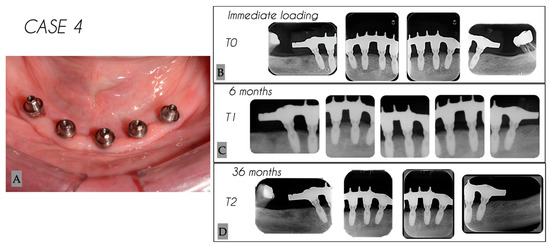

| 4 | Female | 69 | Mandible | 5 |

| Case No. | Tooth No. | Initial MBL (mm) | MBL 6 Months (mm) | MBL 36 Months (mm) | KM 6 Months (mm) | KM 36 Months (mm) |

|---|---|---|---|---|---|---|

| 4 | 35 | 0.54 | 1.22 | 1.35 | 4 | 4 |

| 4 | 31 | 0.58 | 1.01 | 1.07 | 4 | 4 |

| 4 | 33 | 0.84 | 1.45 | 1.6 | 5 | 5 |

| 4 | 43 | 0.57 | 1.18 | 1.67 | 4 | 4 |

| 4 | 45 | 0.47 | 1.98 | 2.17 | 4 | 4 |

| Mean | 0.60 | 1.37 | 1.57 | 4.2 | 4.2 | |